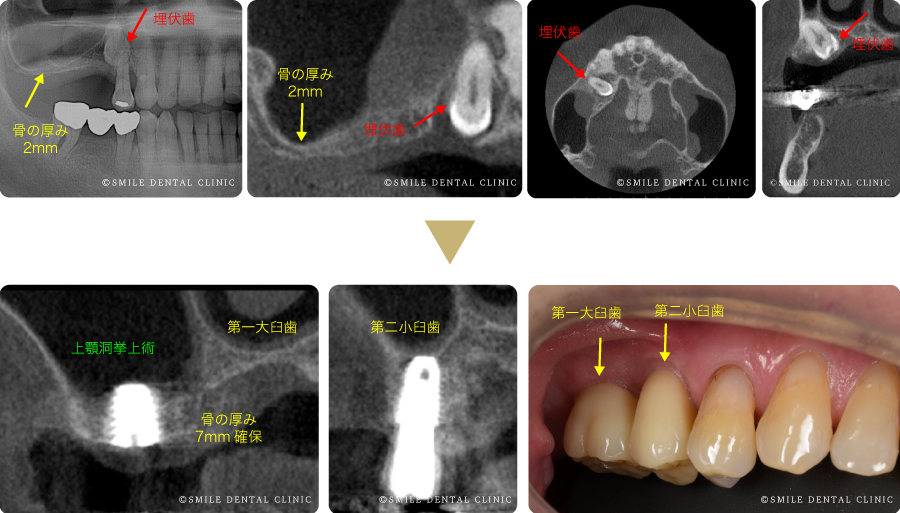

「インプラントの咬合」保母 須弥也 / 細山 愃定価: ¥ 23000+税ISBN 4-87417-933-9クインテッセンス出版株式会社#保母須弥也 #保母_須弥也 #細山愃 #細山_愃 #本 #自然/医療・薬学・健康ほぼ未使用ですので状態は良好ですカバーの背に皺があります。(写真7枚目)ご確認ください。外箱はありません。点検しておりますが見落としがありましたらお許しください。喫煙者ペットおりません。ご覧いただきありがとうございます。